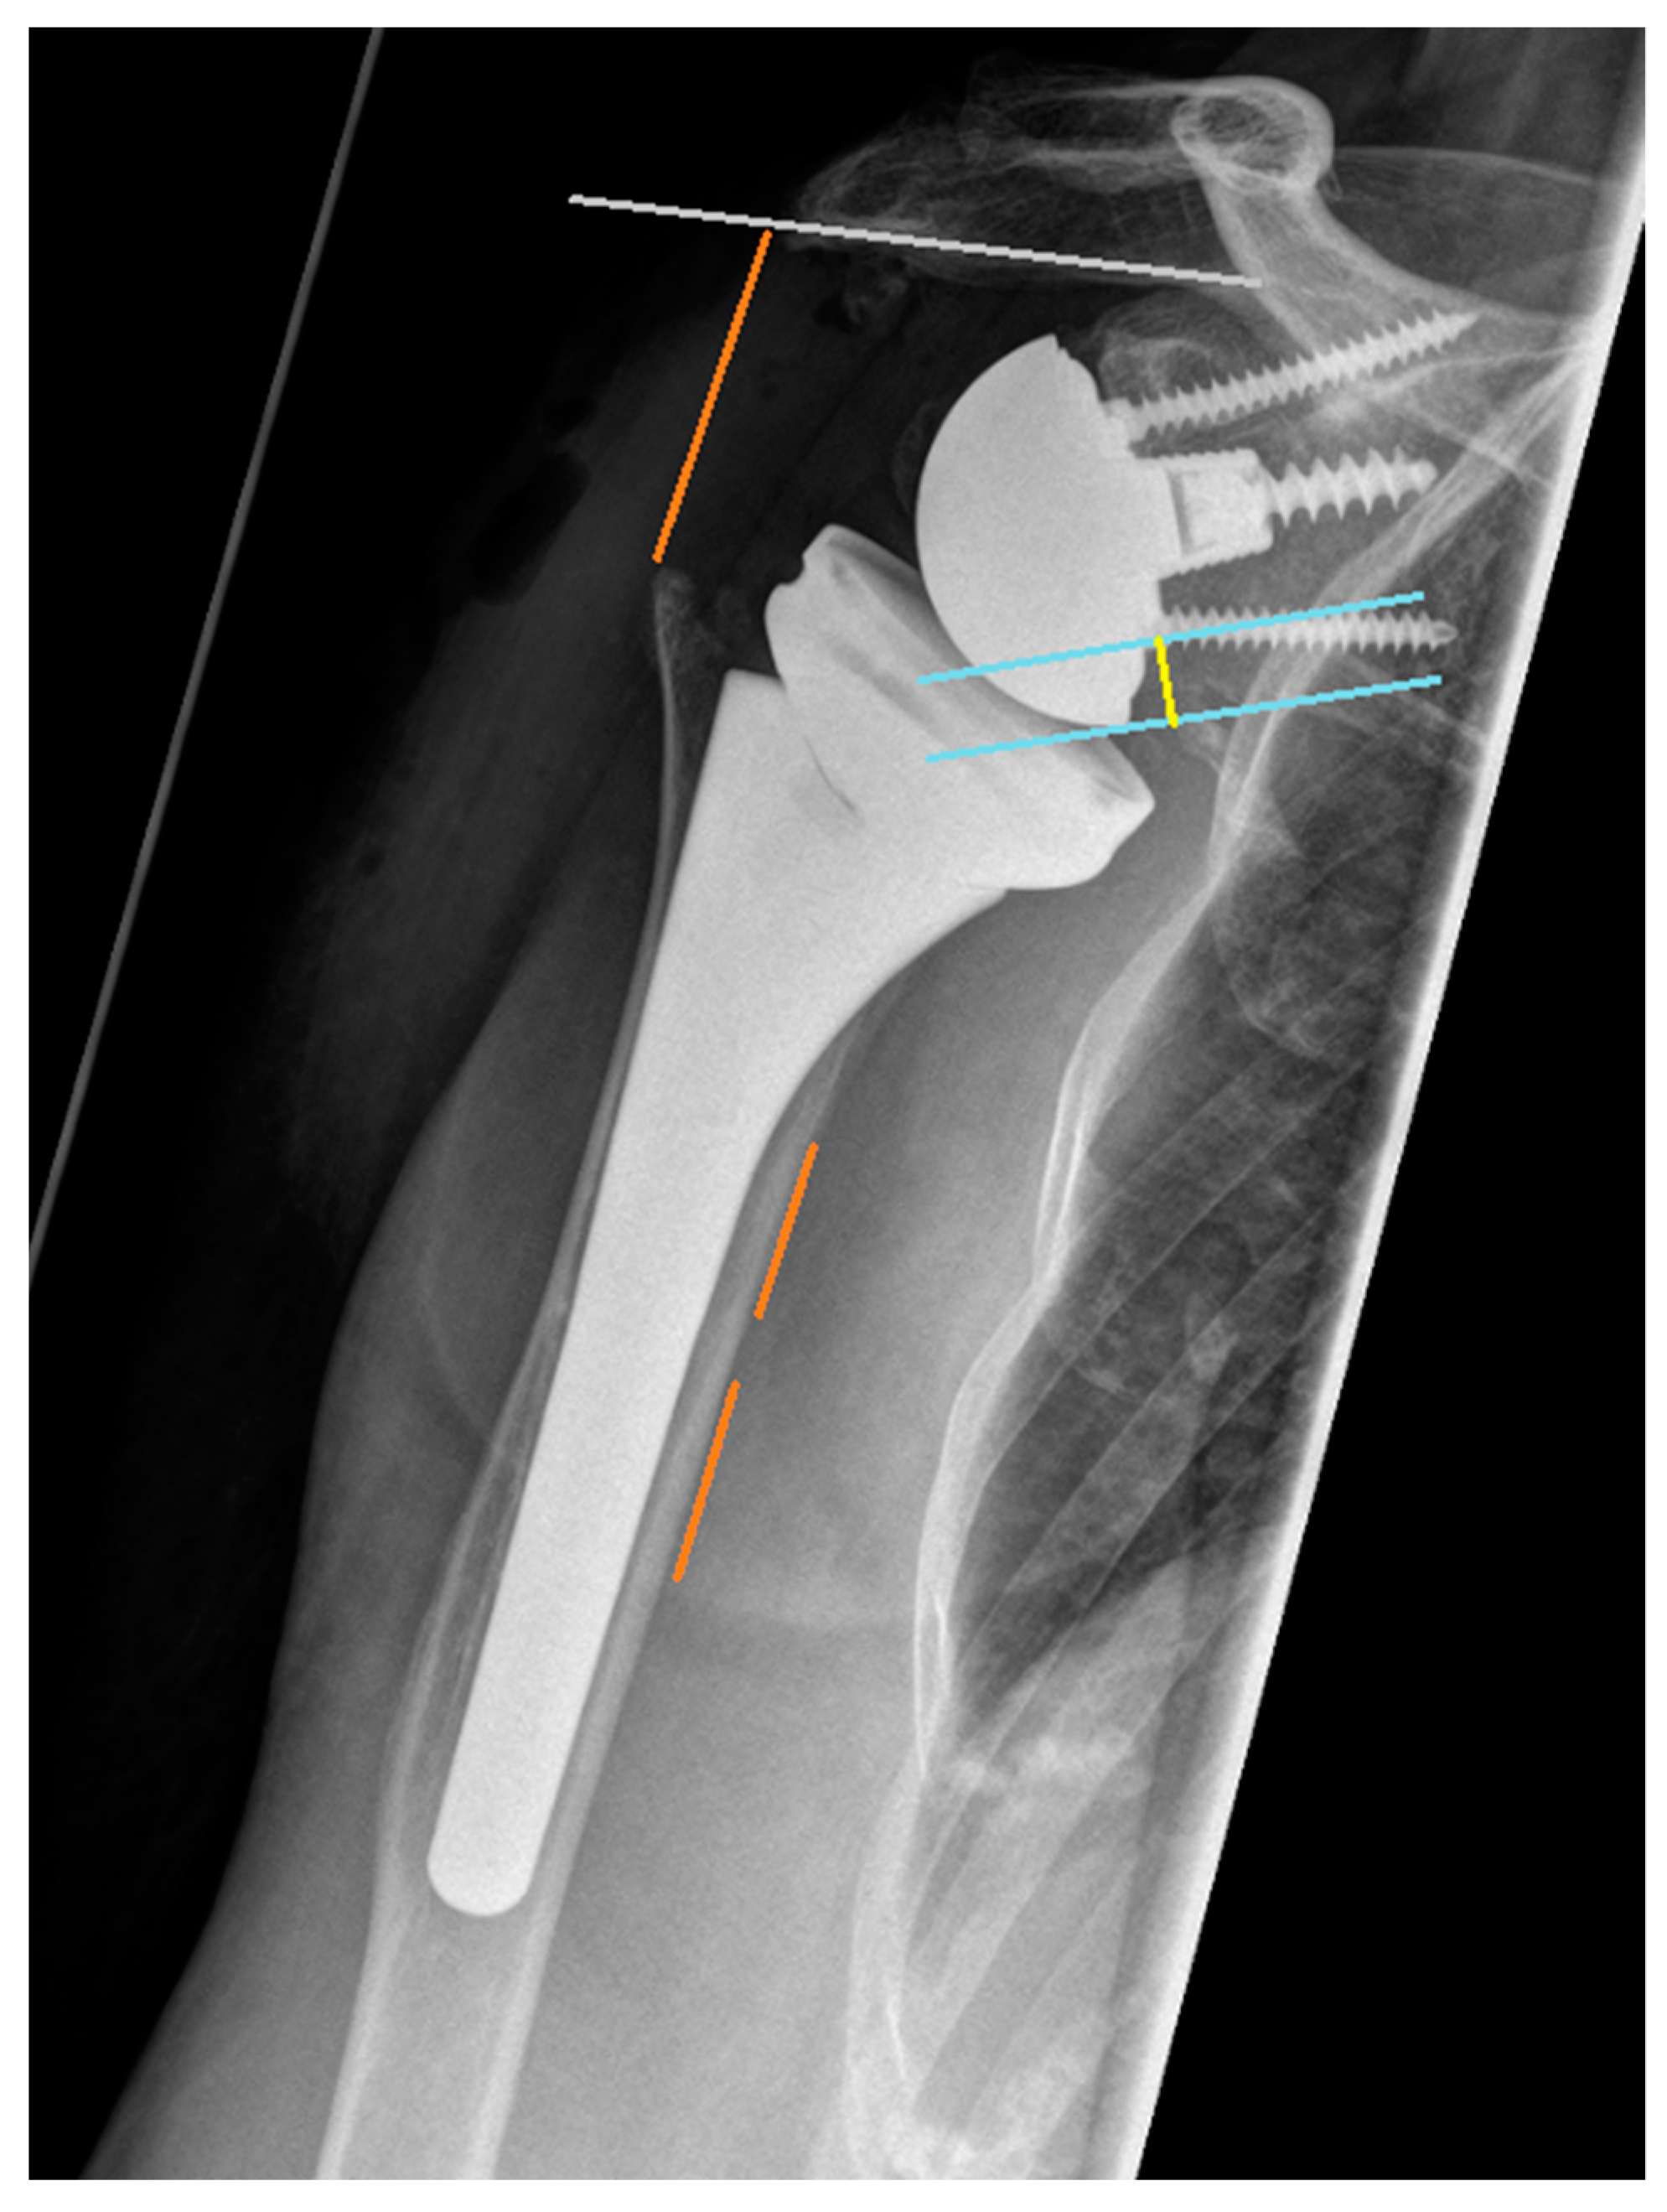

2.4. Radiographic Assessment